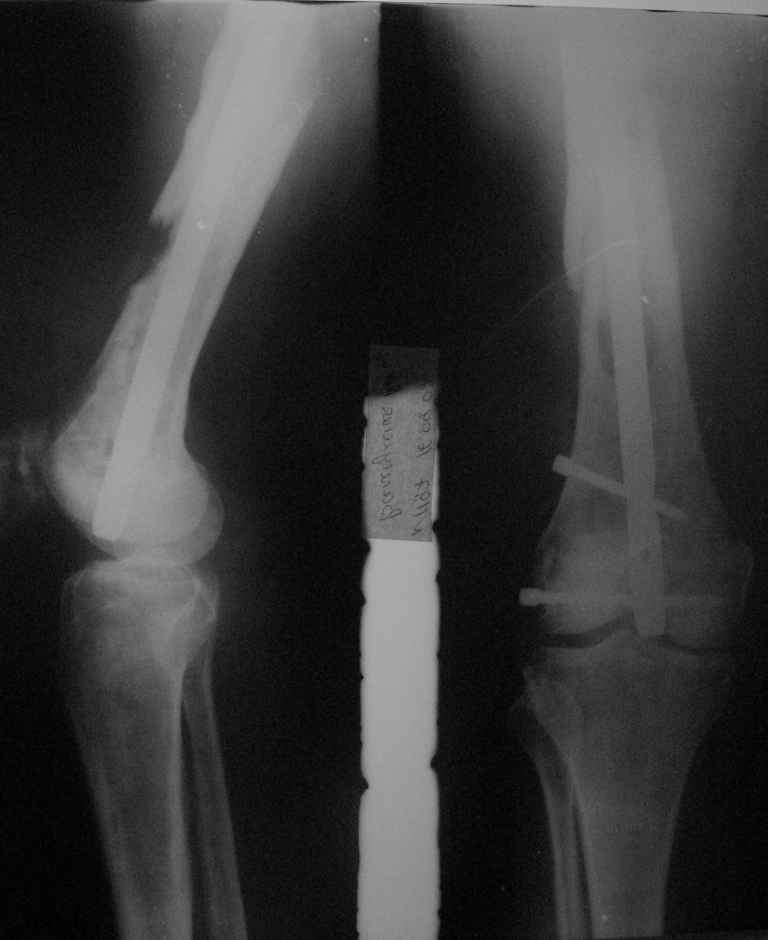

Приветствую, коллеги. 2 года назад пациентке поставлен диагноз саркома бедра,

Реостеосинтез

1.5 года назад произведен синтез для улучшения качества жизни для по поводу патологического перелома на уровне открытой биопсии. Через 4 месяца открытый реостеосинтез с исправлением оси и восстановления опроспособности. В период после перелома лучевой и химиотерапии не получала. Месяц назад появилсь возрастающие боли в суставе. Ходит с тростью. Движения в коленном суставе качательные.На рентгеннограммах после реостеосинтеза намечалась тенденция к сращению. В области операционной раны периодически открывался-закрывался свищ. На последних - кроме миграции гвоздя в сустав - лизис костной мозоли. Можно ли одной из причин миграции считать длительную статическую фиксацию гвоздя? У кого-нибудь есть опыт на каких сроках проводить у онкобольных динамизацию? Что можно сделать для ликвидации боли и поддержания опороспособности конечности? Имеет ли смысл установка более толстого фиксатора без дистального блокирования? И вообще,ставить ли здесь вопрос о сохранении конечности?